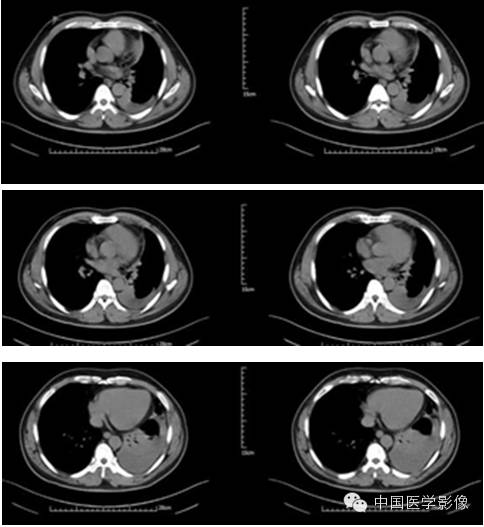

病例2【病史】

患者男,47岁。

患者因“查体发现右纵膈区占位2周”入院。患者无胸痛、胸闷,无发热、盗汗,无咳嗽、咳痰。CT示:右心膈角处新生物,考虑来自叶间裂的炎性假瘤可能性大,不除外其他肿瘤可能。

专科查体:(-)

入院诊断:右下纵膈占位:心包囊肿?炎性假瘤?

【影像资料】

平扫

动脉期

静脉期

延迟期

【病理结果】

孤立性纤维性肿瘤